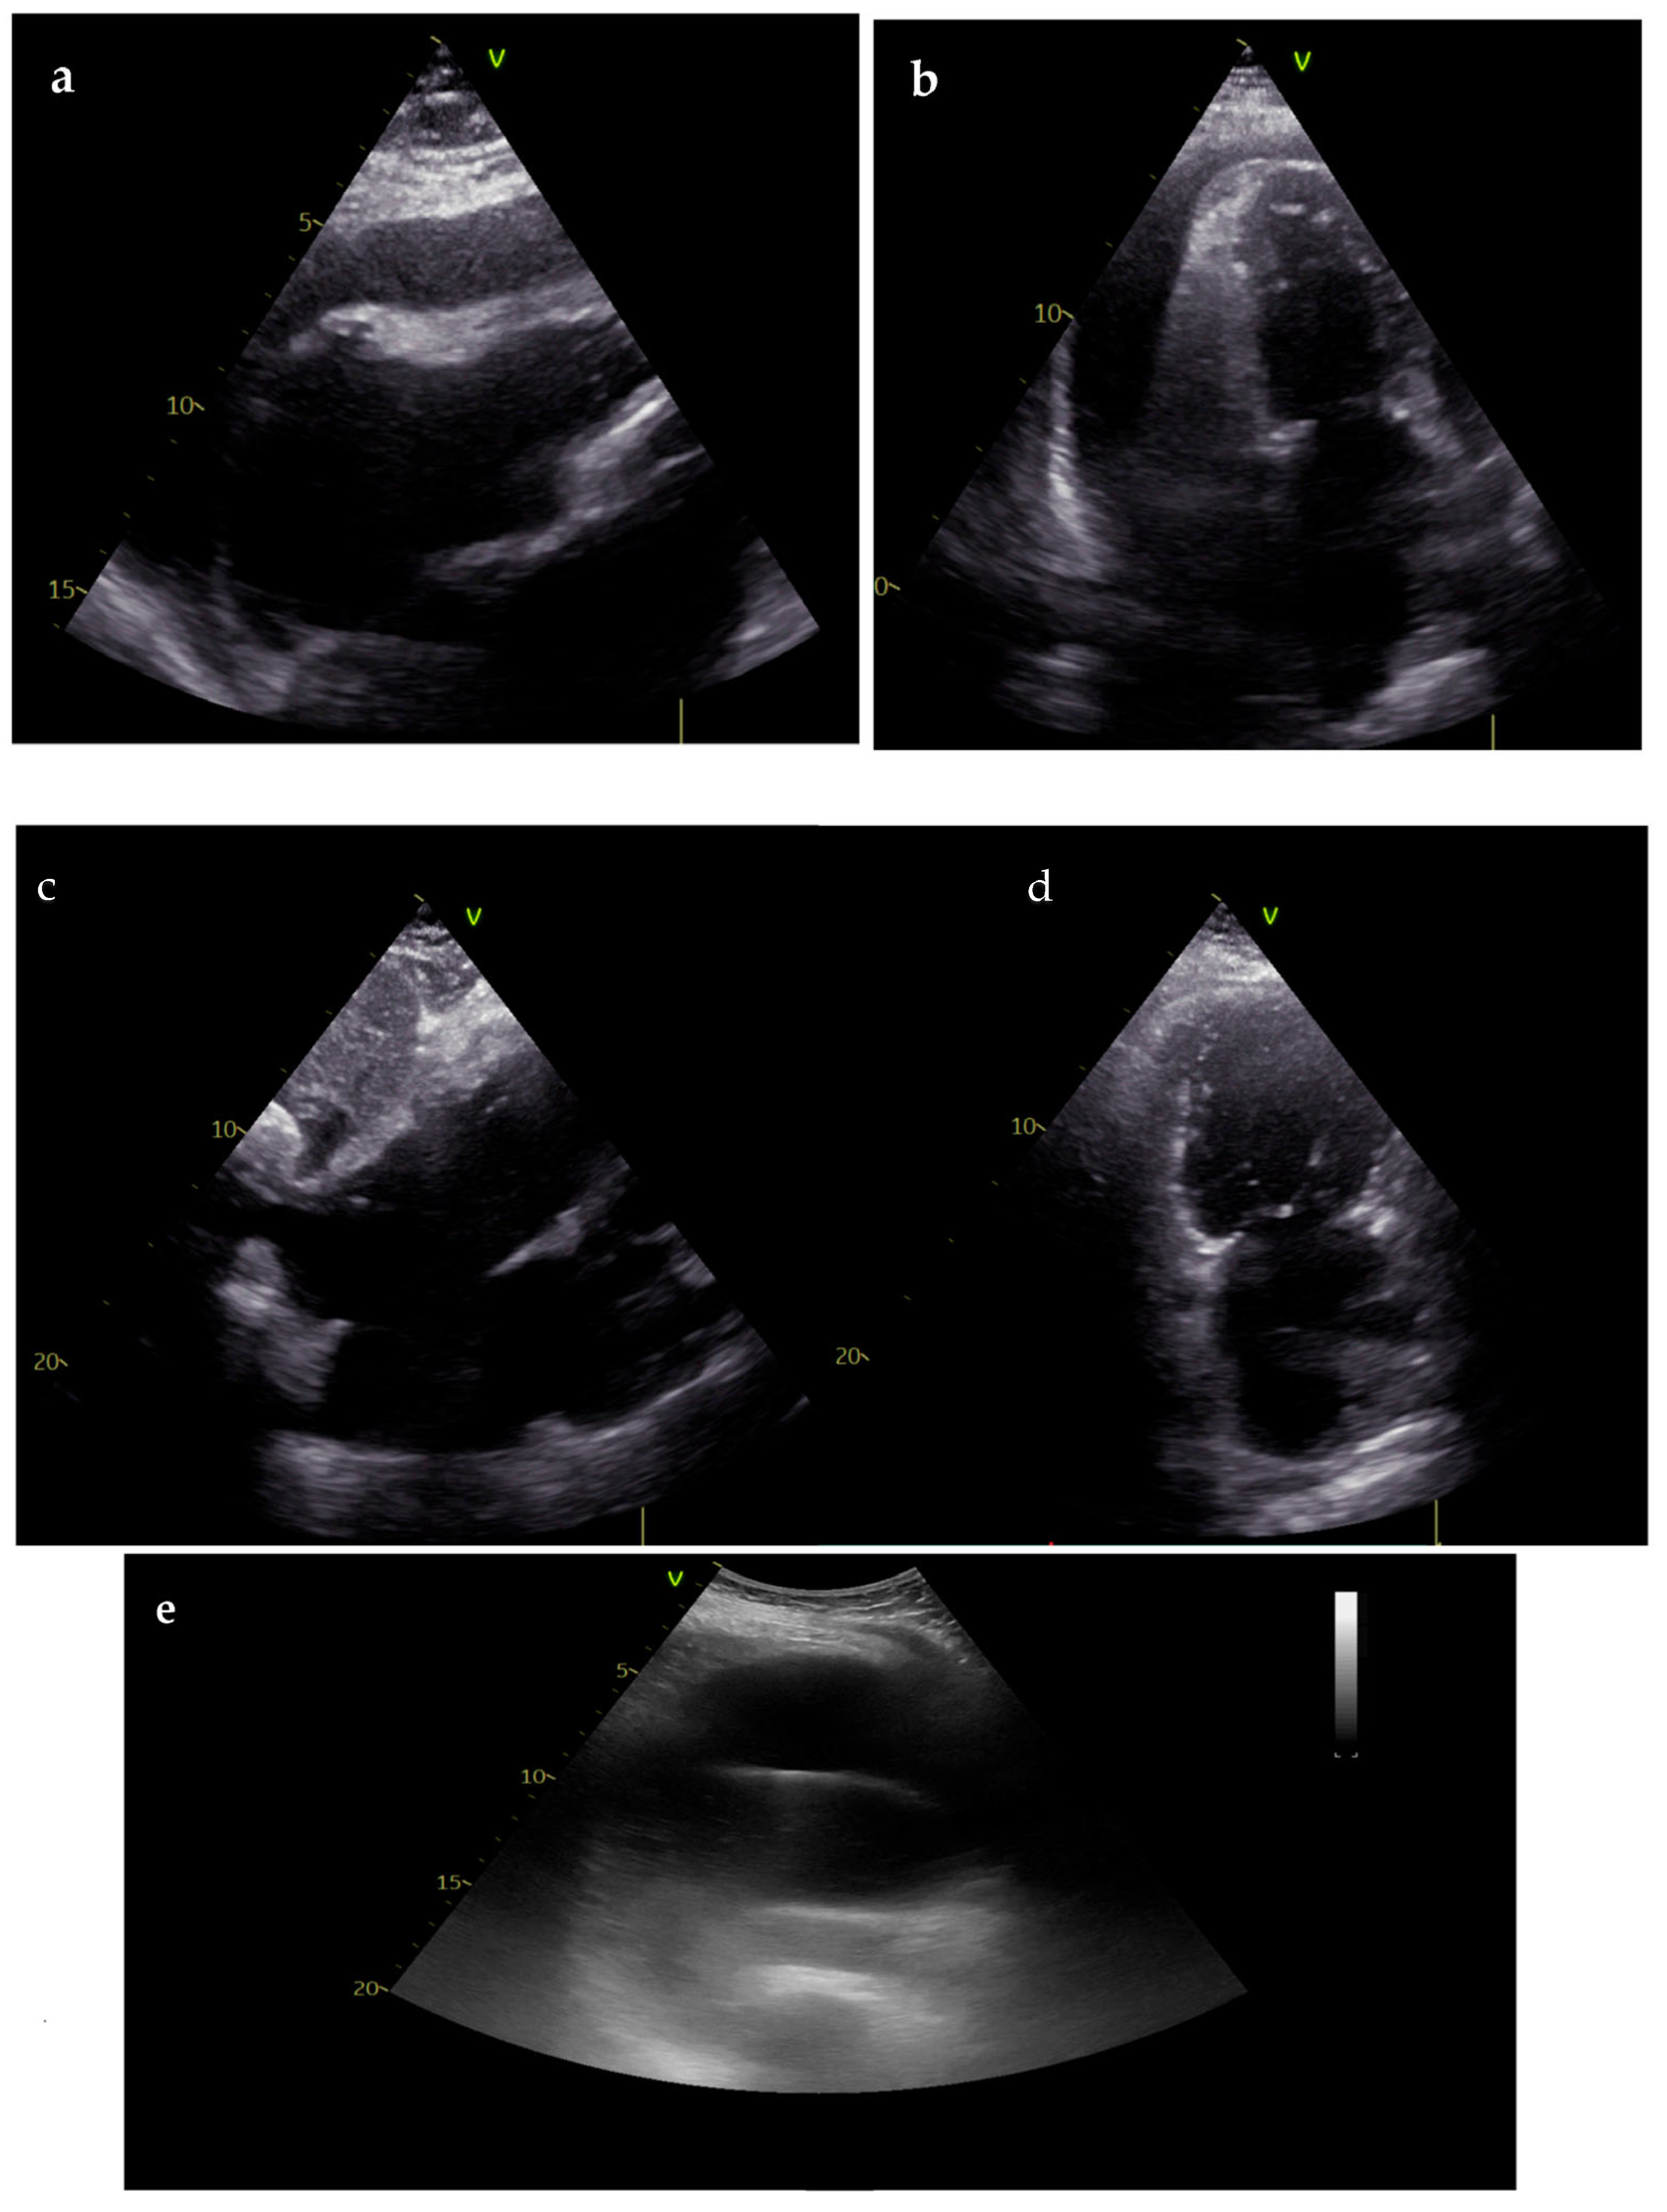

3.2. Role of Non-Cardiac Ultrasounds

- Laursen, C.B.; Davidsen, J.R.; Madsen, P.H. Utility of lung ultrasound in near-drowning victims. BMJ Case Rep. 2012, 2012, bcr0120125687. [Google Scholar] [CrossRef] [PubMed]

- D’andrea, A.; Conte, M.; Cavallaro, M.; Scarafile, R.; Riegler, L.; Cocchia, R.; Pezzullo, E.; Carbone, A.; Natale, F.; Santoro, G.; et al. Transcranial Doppler ultrasonography: From methodology to major clinical applications. World J. Cardiol. 2016, 8, 383–400. [Google Scholar] [CrossRef] [PubMed]

- Beaubien-Souligny, W.; Rola, P.; Haycock, K.; Bouchard, J.; Lamarche, Y.; Spiegel, R.; Denault, A.Y. Quantifying systemic congestion with Point-Of-Care ultrasound: Development of the venous excess ultrasound grading system. Ultrasound J. 2020, 12, 1–12. [Google Scholar] [CrossRef] [PubMed]

- Tavazzi, G.; Spiegel, R.; Rola, P.; Price, S.; Corradi, F.; Hockstein, M. Multiorgan evaluation of perfusion and congestion using ultrasound in patients with shock. Eur. Heart J. Acute Cardiovasc. Care 2023, 12, 344–352. [Google Scholar] [CrossRef] [PubMed]

- Pellicori, P.; Hunter, D.; Khin, H.H.E.; Cleland, J.G.F. How to diagnose and treat venous congestion in heart failure. Eur. Hear. J. 2024, 45, 1295–1297. [Google Scholar] [CrossRef]